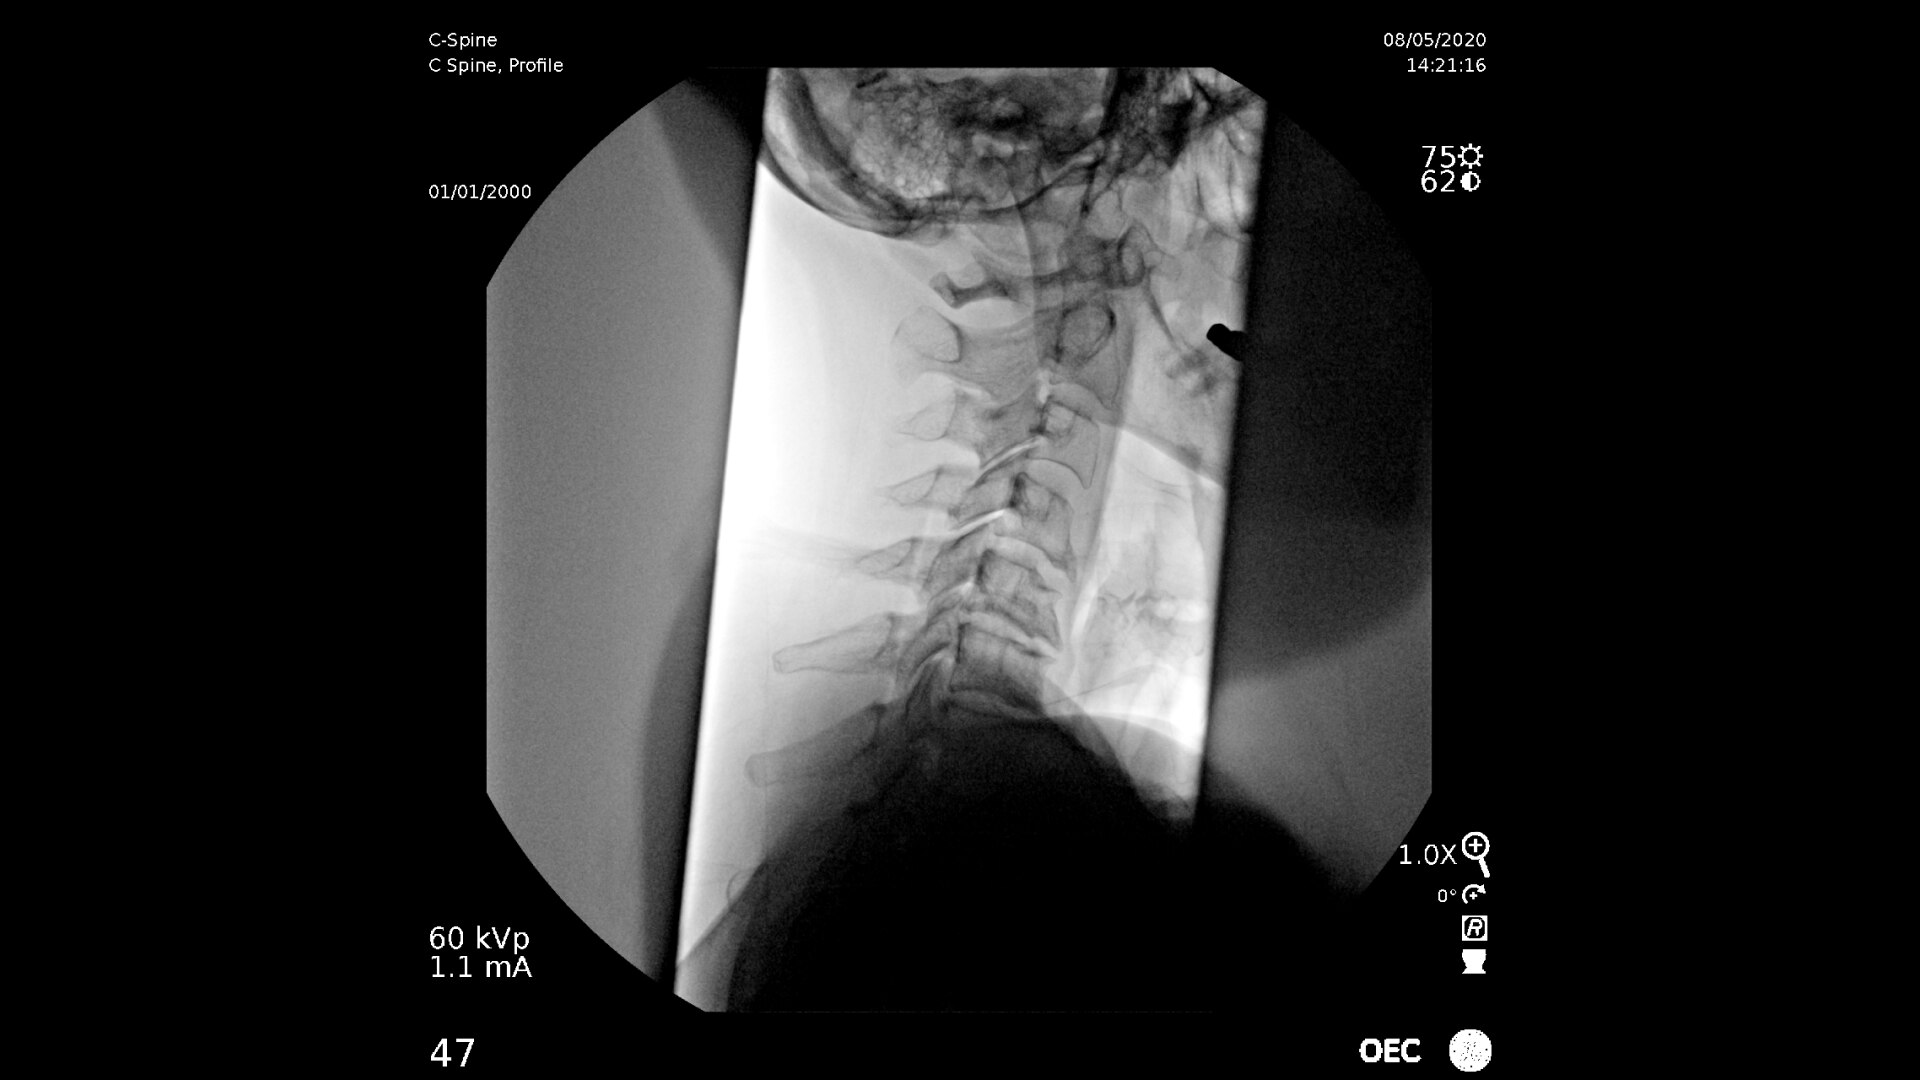

Consistently experience amazing image quality, precision, and efficiency during simple to complex pain management procedures with OEC C-arms.

Achieve precision and efficiency while experiencing the image quality needed during simple to complex pain management procedures with OEC C-arms.

See clear detail captured on a flat panel detector to a 4K display for visualization of anatomical detail.

Live Zoom up to 4Xs to see needle placement, without the use of Mag mode. Live Zoom also enable panning to an area of interest without having to move the base of the C-arm.

Pain management imaging you need

Pain Management procedures require powerful imaging systems.

OEC C-arms perform imaging in a variety of procedures such as:

• Cervical spine pain management